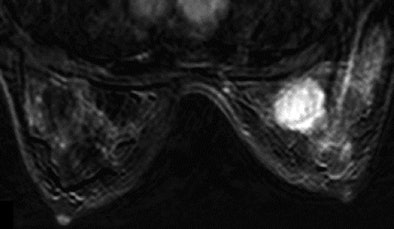

| Thirty-two-year-old woman with ductal infiltrating adenocarcinoma measuring 18 mm in maximum transverse diameter. Axial fused PET/CT images obtained with patient in prone position at time point 1 (above) and time point 2 (below) show corresponding standard uptake values. |

![]() |

| Above, subtracted contrast-enhanced T1-weighted axial MR image shows focal area of intense F-18 FDG uptake and marked gadolinium enhancement in superior inner quadrant of right breast. |